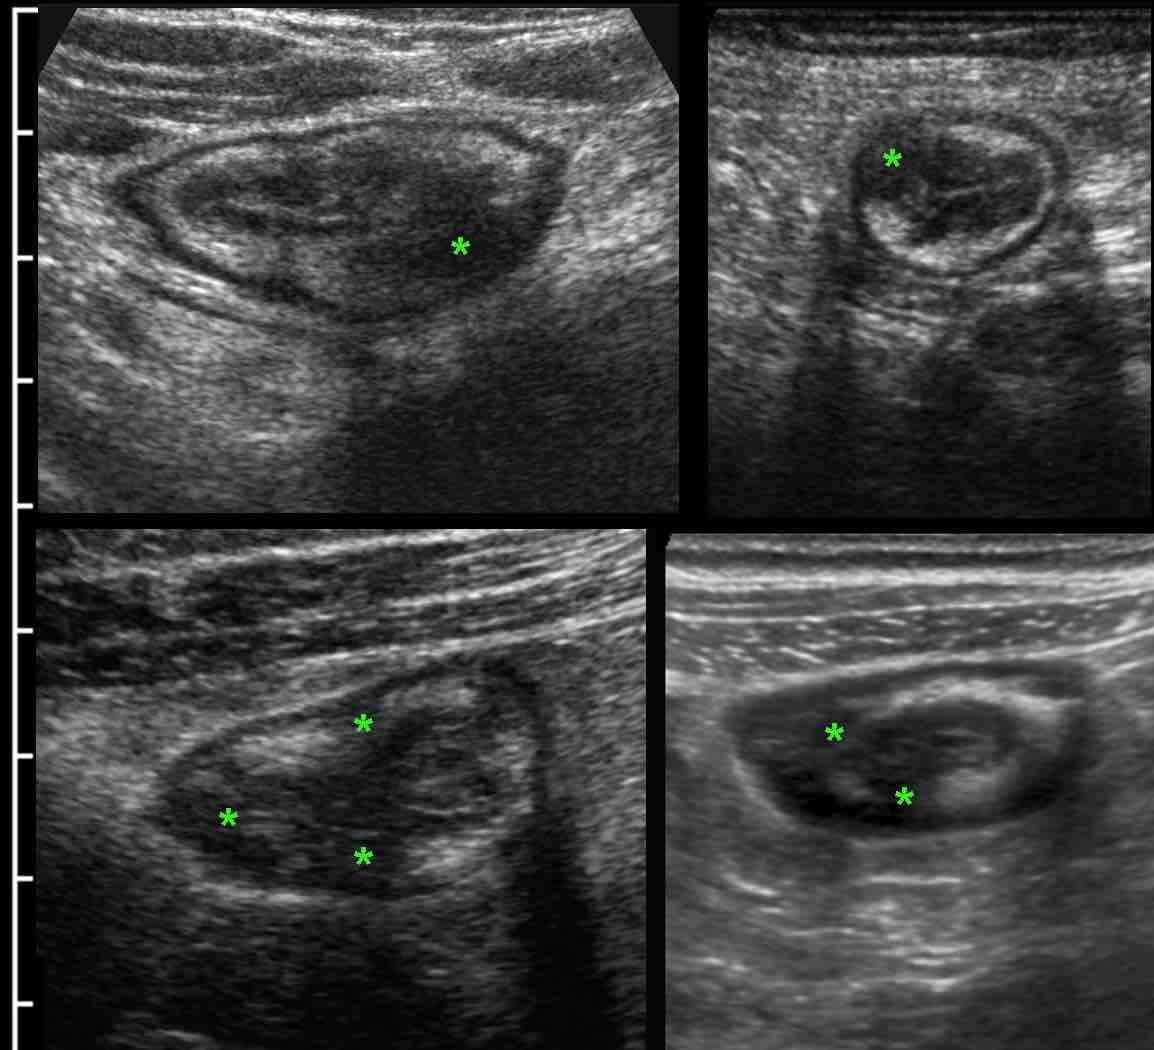

Thông thường, ngay tại lần khám đầu tiên, siêu âm đã bộc lộ “đặc điểm” xuyên thành đặc trưng của bệnh Crohn.

Sự tiến triển xuyên thành này được nhận biết là các thay đổi giảm âm (*) khu trú trong lớp dưới niêm mạc vốn tăng âm, tương quan chặt chẽ với các phát hiện nội soi và các thay đổi mô học viêm hoạt động (4).

Bệnh nhân nam 18 tuổi này nhập viện với các triệu chứng giống viêm ruột thừa cấp và được chụp CT ngay lập tức.

CT cho thấy hình ảnh dày thành hồi tràng rõ rệt và ruột thừa bình thường (không hiển thị ở đây).

Siêu âm tiếp theo cho thấy các thay đổi giảm âm xuyên thành đặc trưng điển hình trong lớp dưới niêm mạc tăng âm, xác nhận chẩn đoán viêm hồi tràng do Crohn.

Lưu ý độ phân giải hình ảnh vượt trội của siêu âm so với CT.

Ở những bệnh nhân có bệnh Crohn hoạt động rõ ràng, cấu trúc siêu âm bình thường của thành ruột có thể bị mất lan tỏa.

Lưu ý mô mỡ tăng âm (fat) xung quanh hồi tràng, đại diện cho mạc treo và mạc nối đang viêm, đang cố gắng bao bọc lại vị trí thủng sắp xảy ra.

Trong những trường hợp như thế này, hình thái thay đổi và lòng ruột hẹp lại có thể bắt chước hình ảnh ác tính.